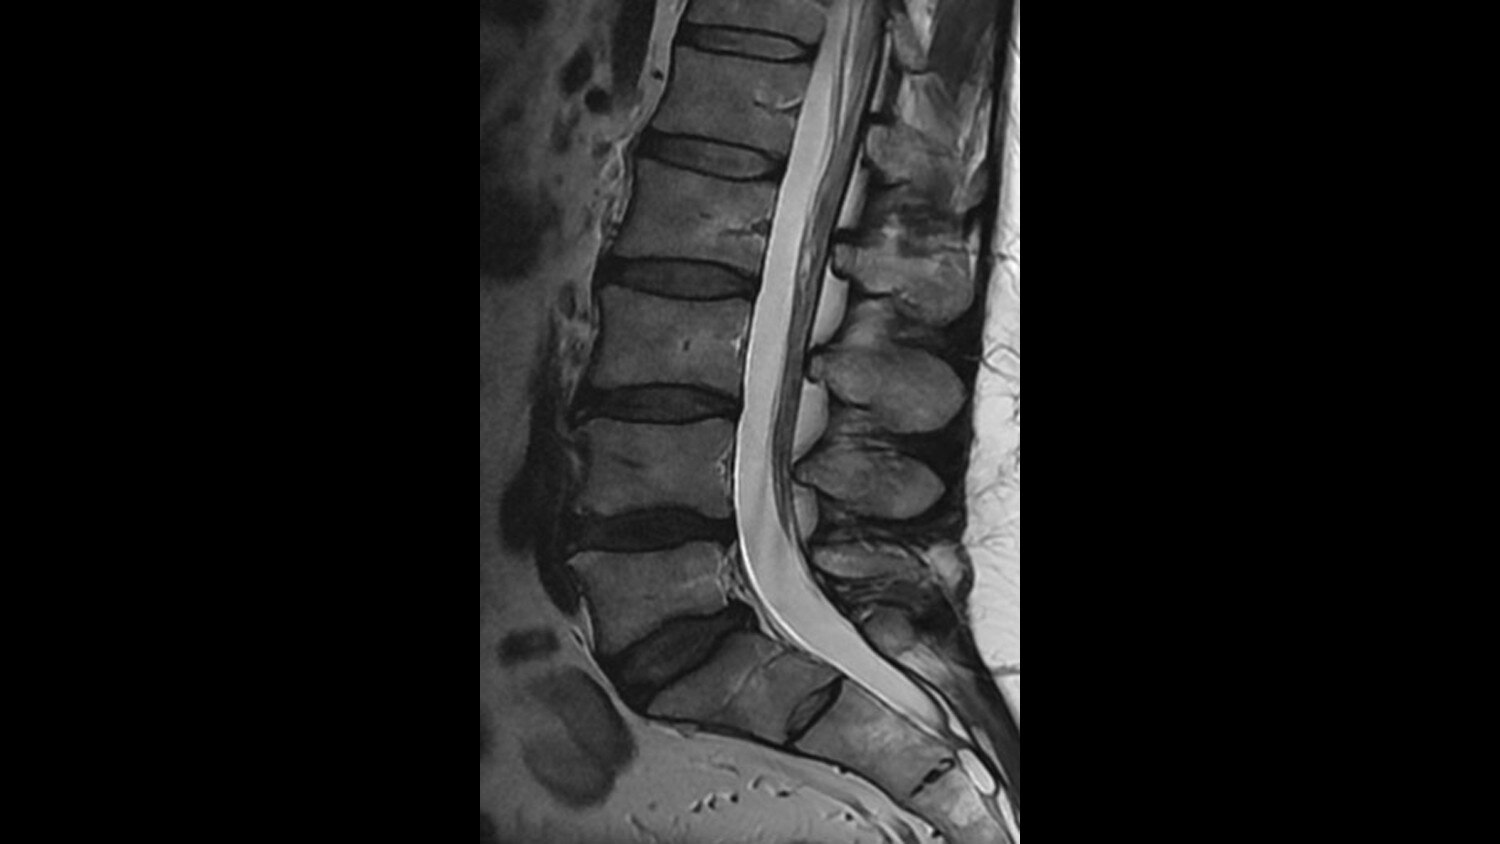

Its full 3.0T magnet and 70 cm bore work together to generate extraordinary image quality without compromises. The result for clinicians is new levels of diagnostic performance.

Magnet A new, light-weight magnet with a compact footprint that supports a 70 cm patient gantry and offers a large 50 x 50 x 50 cm useable field of view with excellent homogeneity for uncompromised coverage and quality.

A large usable field of view is needed to properly image off-center anatomy such as a shoulder or hip. So the Discovery* MR750w features a 70 cm flared, open bore design with a large 50 x 50 x 50 cm field of view.

Gradients and RF body coils are water and air-cooled for optimum duty-cycle performance, short repetition time (TR) and echo time (TE), producing sharp and clear images.